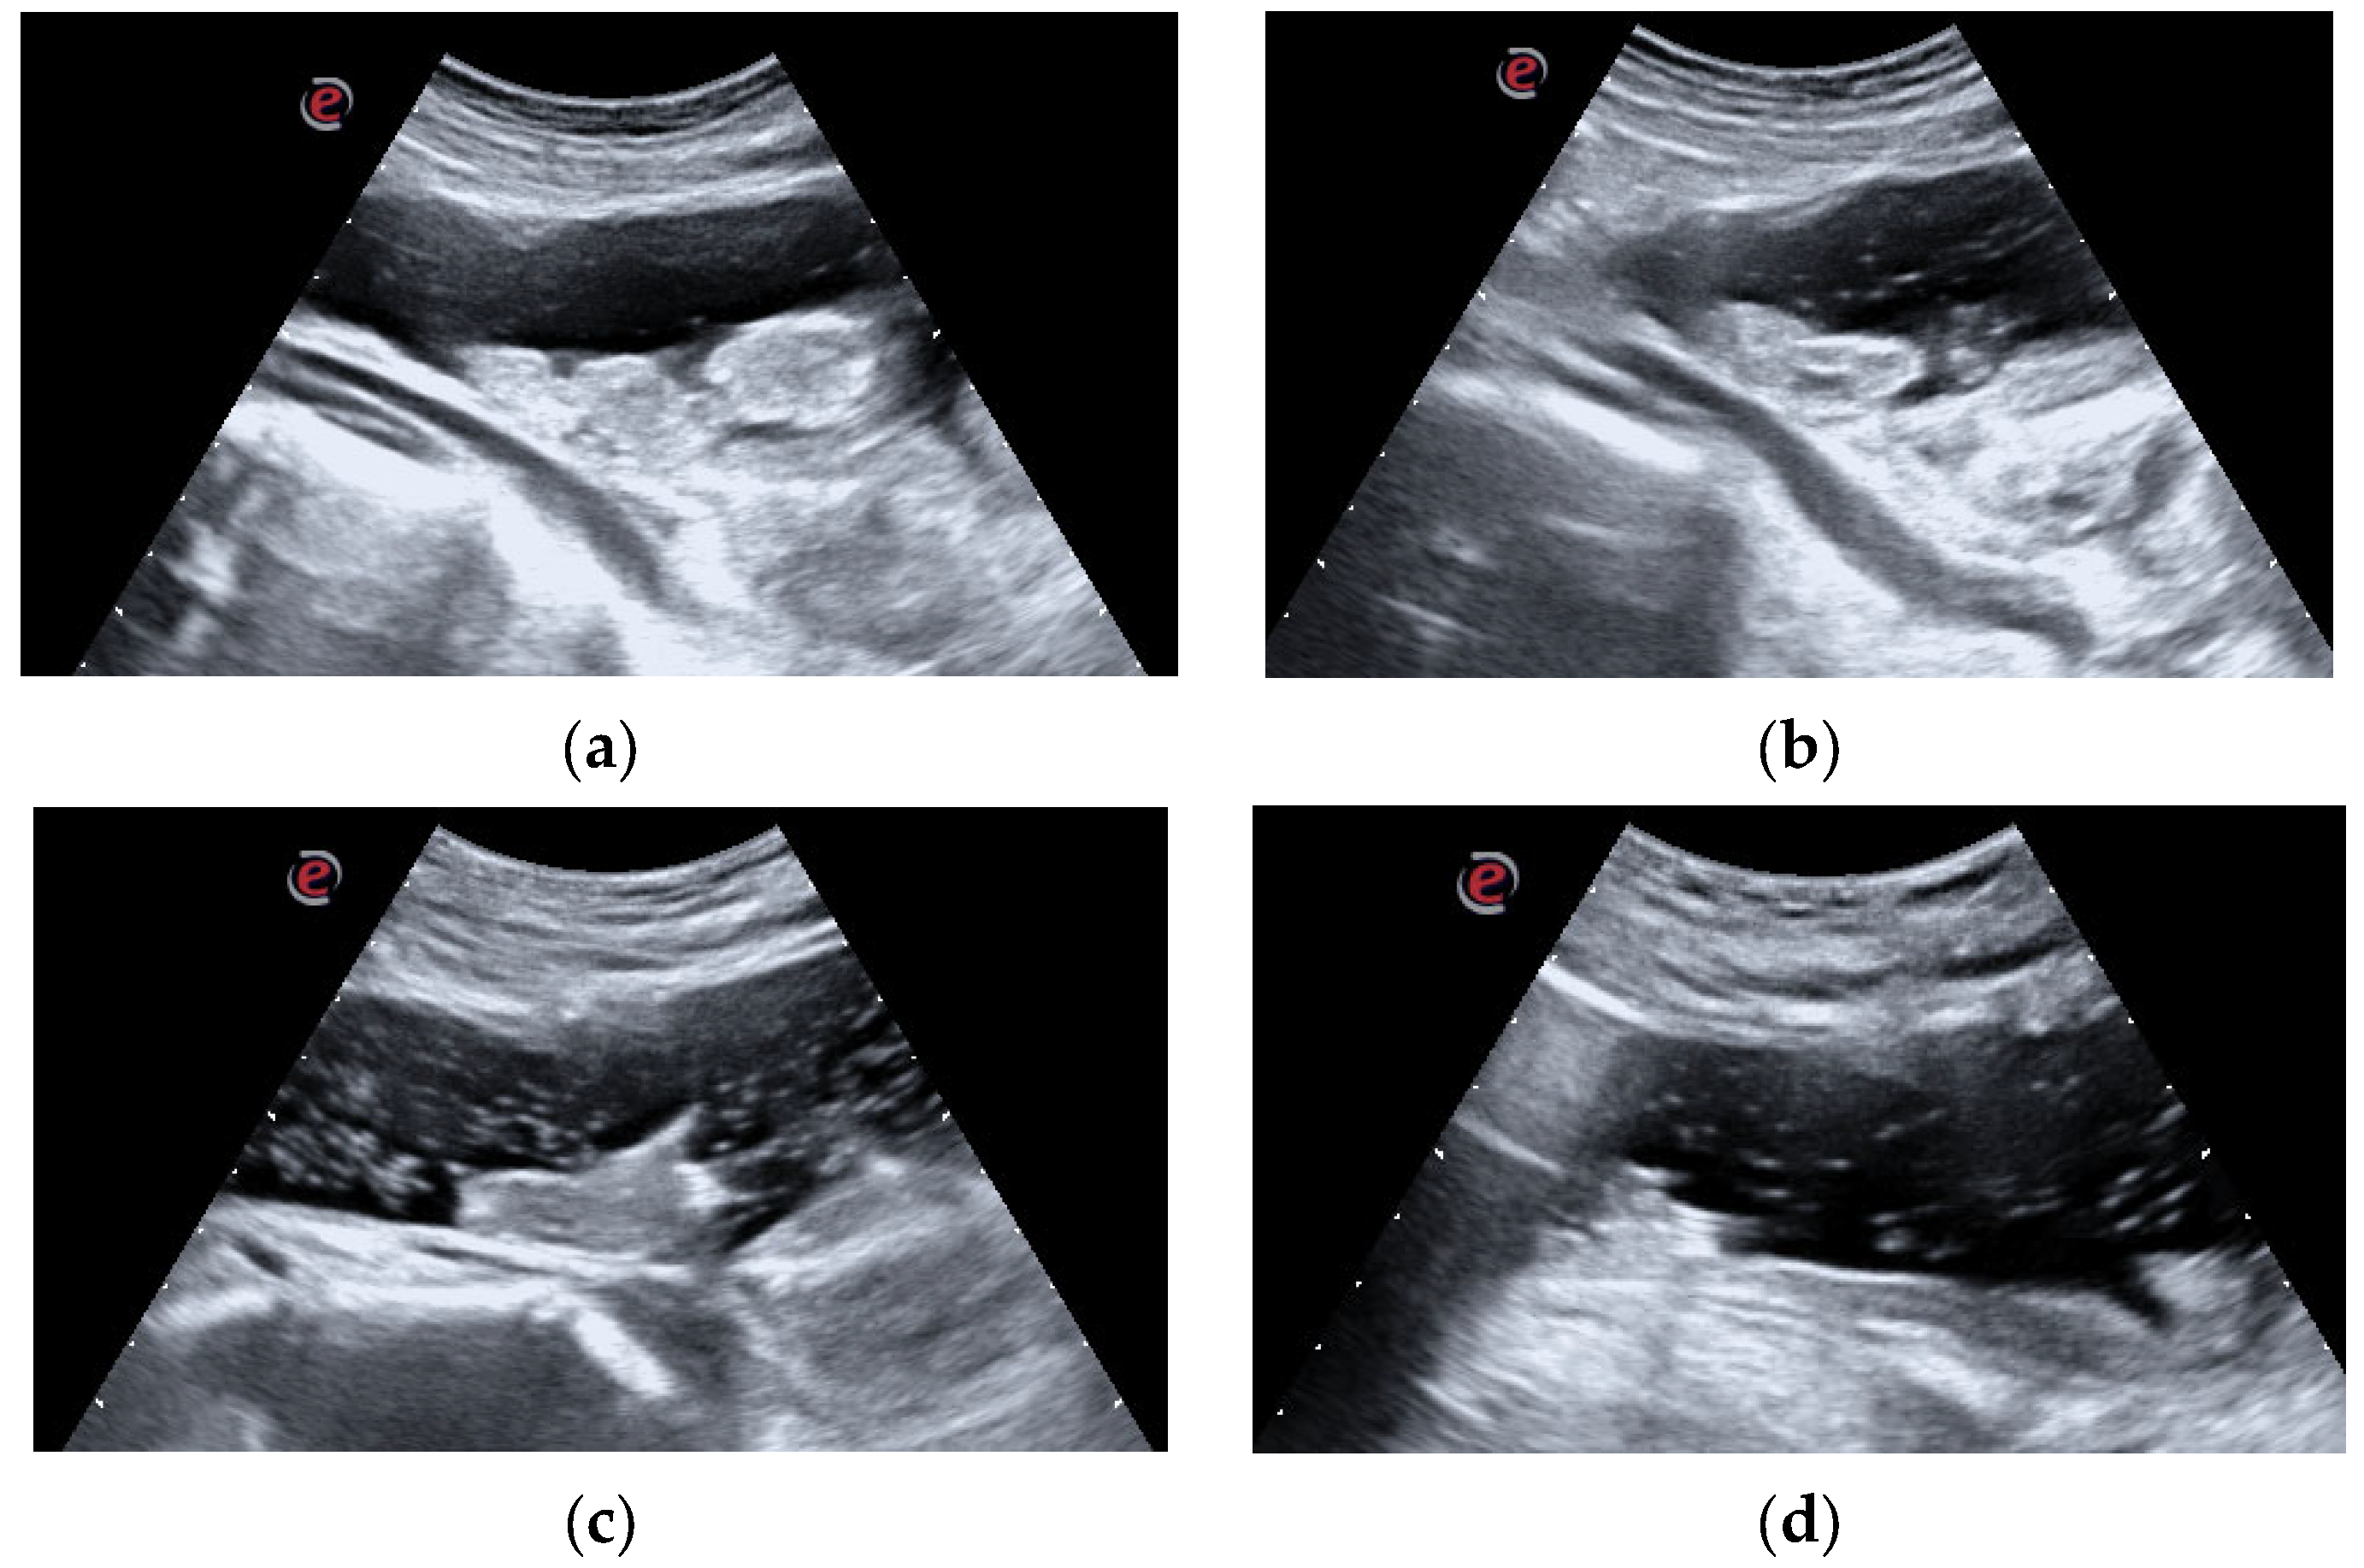

The preliminary endoscopic evaluation confirmed the hematic nature of the clot without any sign of active bleeding (Figure 2a,b).

(a,b). Endoscopic view: endoscopic appearance of the clot. The light red shade of color suggests the late formation of the clot and, thus, its friability. No signs of active bleeding are visible. The 30° endoscopic optics ensured correct angulation of the view, overcoming the reduction in movement caused by the Mitrofanoff channel insertion angle.